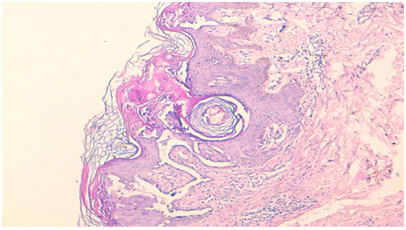

A 61 year-old female patient, with no medical or familial history, presented to the Department of Dermatology of our Hospital, with a 3year history of persistent pruriginous and malodorant papules on the body. These lesions were insidious in onset and were neither painful nor associated with burning sensation. They became more itchy and infected during summer. There were no associated systemic complaints, nor any family history of hereditary diseases. Physical examination showed a grayish colored warty and hyperkeratotic papules and plaques, with rough and spiny surface and fetid odor, localized on post auricular areas, neck, intermammar folds, along with subungueal keratosis and trachyonychia (Figure 1) (Figure 2). There was no mucosal involvement. Dermoscopy showed yellowish polygonal structures of various size surrounded by a thin whitish halo (Figure 3). Systemic examination didn’t reveal any abnormality. An incisional biopsy from the lesions was taken for microscopic examination which showed characteristic histopathological findings consistent with the diagnosis of Darier’s disease (Figure 4). Given the presence of highly suggestive lesions with clinical and histopathological examination, a final diagnosis of Darier’s disease was made. The patient was then treated with systemic alitretinoin with no major side effects. She was also encouraged to avoid triggering factors such as UV exposure, heat, and trauma and to daily apply topical emollients. She is on constant review and follow-up with mild improvement.

Figure 4 Histological picture showing hyperkeratosis, suprabasal clefts with acantholytic dyskeratosis, and corps ronds in the granular layer. (Hematoxylin–eosin, original magnification*40).